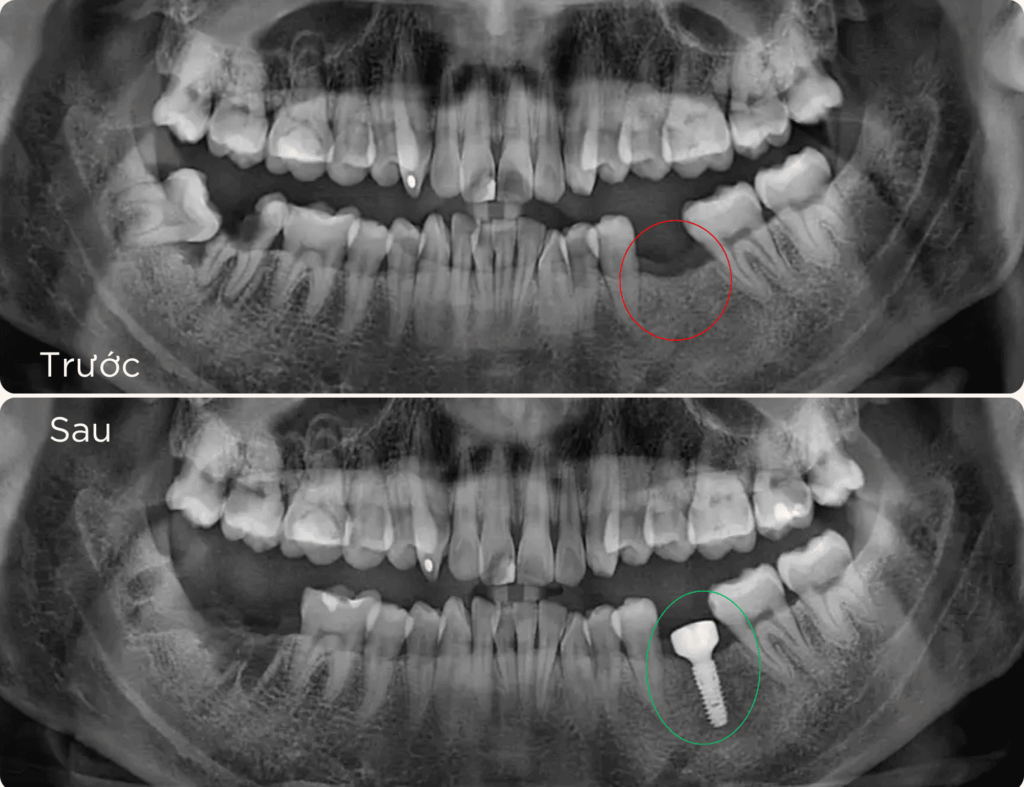

Trồng răng Implant 1 răng là phương pháp phục hồi răng mất tiên tiến, sử dụng trụ chụ chân răng nhân tạo – Implant từ titanium cấy vào xương hàm để thay thế chân răng đã mất. Sau đó, một mão răng sứ được gắn lên trụ, tạo ra chiếc răng mới với hình dáng và chức năng giống như răng thật.

– Mất 1 răng gần đây : Muốn khôi phục lại để ăn nhai thoải mái, giữ nụ cười đẹp và tự tin.

– Mất răng lâu năm: Răng xung quanh xô lệch, sai khớp cắn, ảnh hưởng ăn nhai và thẩm mỹ.